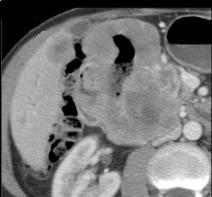

Tumeur de GIST

polylobulaire de jejunum avec nodule metastasique du

foie droit ( extension metastasique hepatique ) |